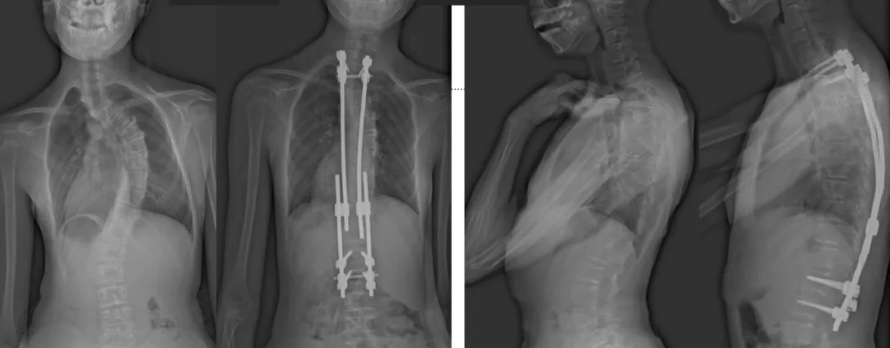

白瑪?shù)恼恍g(shù)前、術(shù)后對比圖(左側(cè));側(cè)位術(shù)前、術(shù)后對比圖(右側(cè))

術(shù)后第二天,白瑪就下地活動(dòng)了。媽媽驚喜地發(fā)現(xiàn),白瑪一下子“長高”了近十厘米,重新抬起了頭,挺直了脊梁,肩膀也不歪了,可謂“脫胎換骨”。媽媽激動(dòng)地錄制了一段白瑪走路的身影,把喜悅分享給全家。白瑪?shù)男g(shù)后檢查也提示,手術(shù)成功,恢復(fù)良好。

白瑪今年10歲,正在讀小學(xué)。媽媽發(fā)現(xiàn),白瑪經(jīng)常歪著肩膀,在反復(fù)提醒“站直了,別歪著”后,情況也沒有改善。近半年來,白瑪?shù)挠覀?cè)肩胛骨逐漸向后凸出。到醫(yī)院檢查后發(fā)現(xiàn),白瑪?shù)男刈荡嬖诿黠@的側(cè)凸畸形,是早發(fā)型特發(fā)性脊柱側(cè)凸。由于側(cè)凸較為嚴(yán)重,已經(jīng)失去了支具治療的機(jī)會(huì)。小白瑪才10歲,隨著身體的不斷成長,她的脊柱會(huì)越來越彎,肩膀會(huì)越來傾斜。這不僅影響體態(tài)和外觀,也可能限制心、肺等內(nèi)臟器官的發(fā)育,導(dǎo)致心肺功能下降、肢體活動(dòng)不便,出現(xiàn)癱瘓,甚至死亡。對于白瑪這種情況,只能利用手術(shù)治療來矯正脊柱、阻止骨骼畸形進(jìn)展。